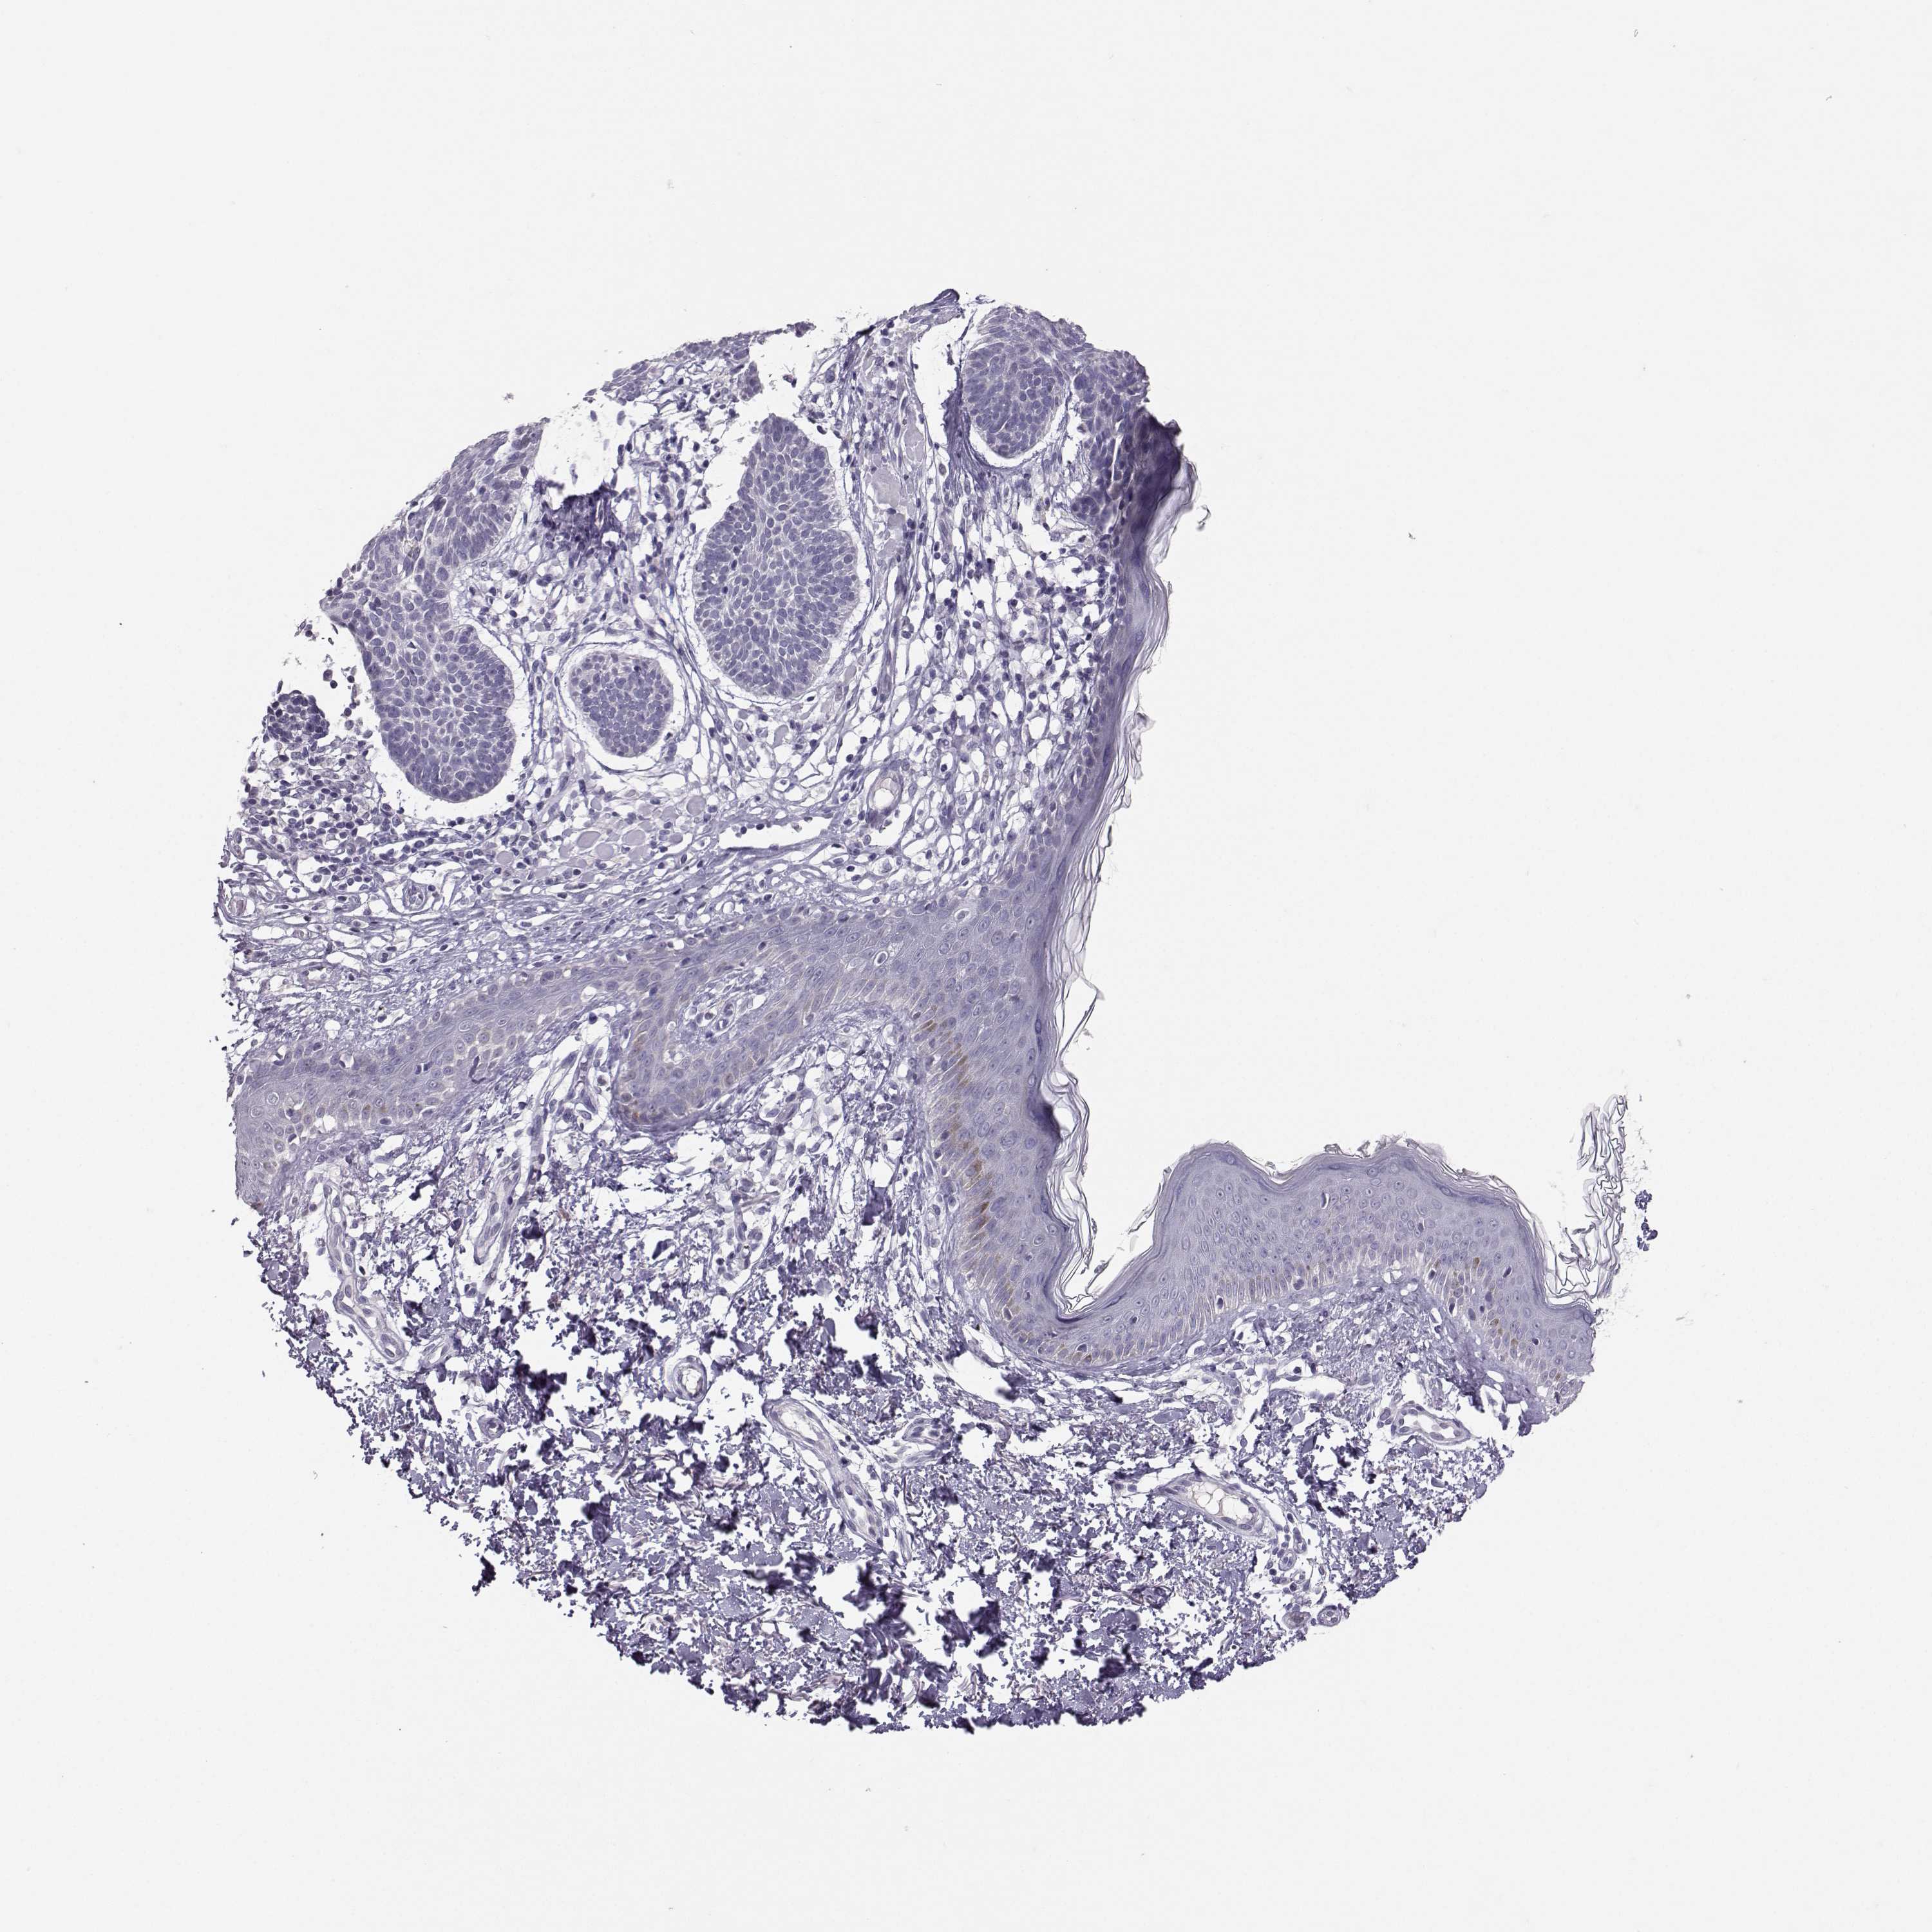

Basal cell and squamous cell cancer

SKIN CANCER - Protein expressioni

A mouse-over function shows sample information and annotation data. Click on an image to view it in a full screen mode. Samples can be filtered based on level of antibody staining by selecting one or several of the following categories: high, medium, low and not detected. The assay and annotation is described here.

Each image is clickable and will lead to virtual microscopy that enables deeper exploration of all samples and also displays staining intensity scores, fraction scores and subcellular localization as well as patient and tissue information for each sample.

Antibody HPA014314

Squamous cell carcinoma in situ, NOS